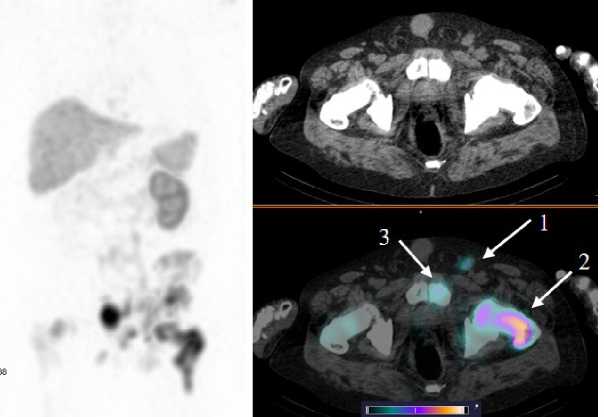

Рис. 4. MIP-реконструкция, КТ и совмещенное ОФЭКТ/КТ изображение больного кастрат-резистентным раком предстательной железы с множественными метастазами в кости через 2 ч после инъекции [99mTc]Tc-HYNIC-PSMA. На ОФЭКТ-КТ-изображении стрелкой отмечено накопление РФЛП в патологических очагах: L5 (1) SUVmax 22,8; боковые массы крестца справа (2) SUVmax 9,7; подвздошная кость справа (3) SUVmax 13,4; подвздошная кость слева (4) SUVmax 10,4

Fig. 4. MIP reconstruction, CT and SPECT/CT image of a patient with castrate-resistant prostate cancer with multiple bone metastases 2 hours after injection of [99mTc]Tc-HYNIC-PSMA. Accumulation of radiopharmaceutical in the pathological areas is indicated by the arrow on the SPECT-CT image: L5 (1) SUVmax 22.8; lateral masses of the sacrum on the right (2) SUVmax 9.7; ilium on the right (3) SUVmax 13.4; ilium on the left (4) SUVmax 10.4